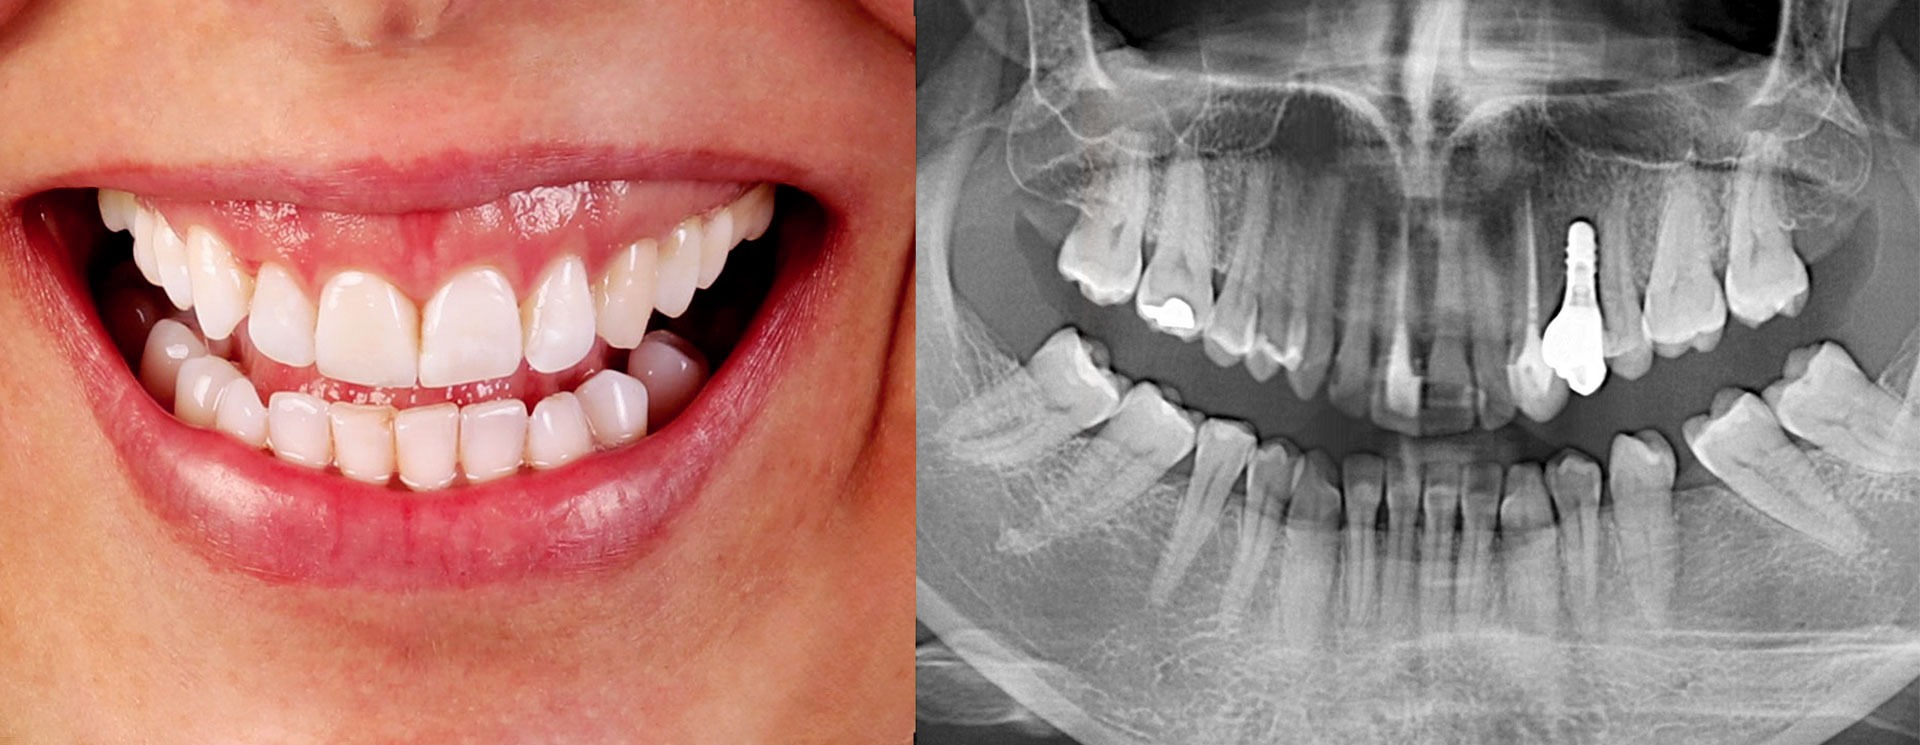

A combinação da reabilitação oral estética e a implantologia pode mudar radicalmente o seu sorriso, aumentando ao mesmo tempo a capacidade de mastigação, contribuindo para uma melhor qualidade de vida.

O implante dentário colocado na estrutura óssea dos maxilares funciona como uma nova “raiz” (porção invisível do dente) que, ao cicatrizar, funde-se com seu corpo e atua como uma raiz natural.

A funcionalidade e o aspecto visual caminham lado a lado: uma restauração implantossuportada meticulosamente elaborada, é colocada repondo a estrutura dentária em falta, assemelhando-se a um dente natural.